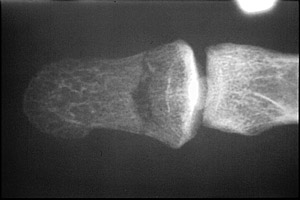

- Click on the image for a larger versionBLateral radiograph of the first digit. There is a depressed fracture of the distal phalanx.